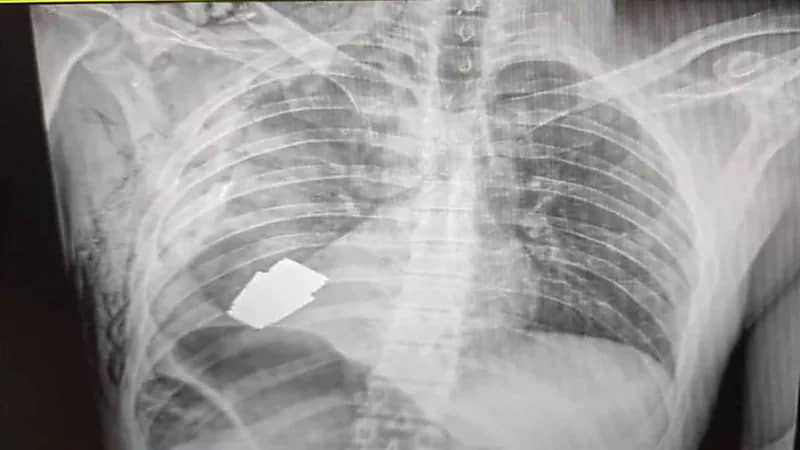

استخراج قنبلة حية من جسد جندي أوكراني